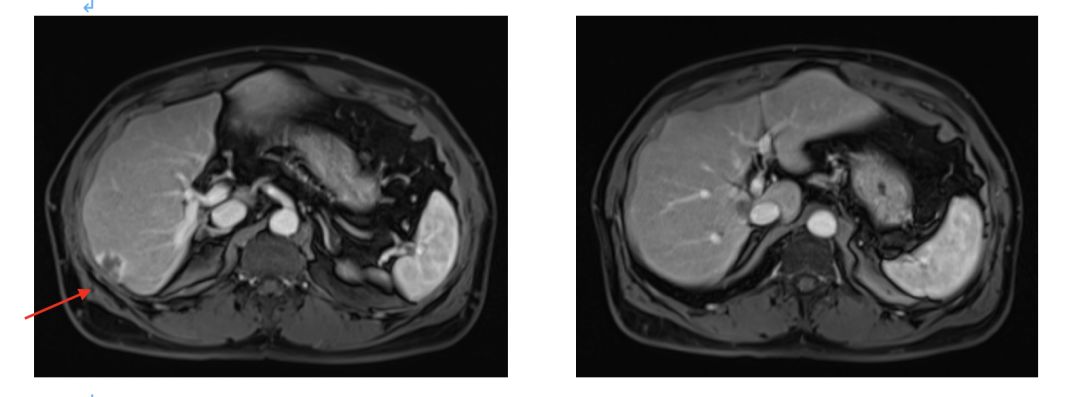

2015.6.16 行肝脏病灶手术+射频治疗,术中B超探查:6个病灶;

见肝脏表面见灰白色转移灶3枚,直径约0.5cm;

肝右后叶近肝门区可扪及质硬肿块约3cm,位于门静脉与腔静脉之间;

肝右叶近膈顶处及肝左叶肿块各一枚,大小约1cm;

射频消融三处:肝S8、S1及S2转移灶。

2016.4.28肝脏MRI:治疗后改变。

2017.6复查肝脏再次出现新病灶,右后叶包膜下边缘见2.2cm*1.4cm强化结节。